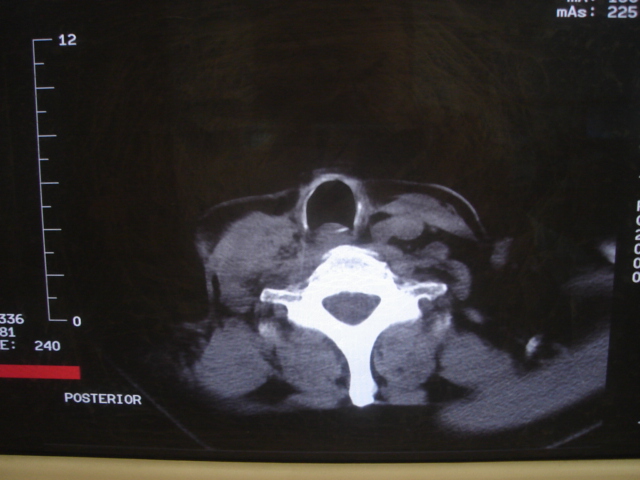

标题: CT18584:甲状腺Ca 喉转移?

患者 男 61  甲状腺ca术后7年 颈部淋巴结转移

颈部多个淋巴结增大,结合甲状腺ca术后7年病史考虑转移。

结合病史符合甲状腺ca术后颈部淋巴结转移

1)右侧颈部淋巴结转移瘤。2)右侧声带新生物,性质待定;建议喉镜检查(活检)。